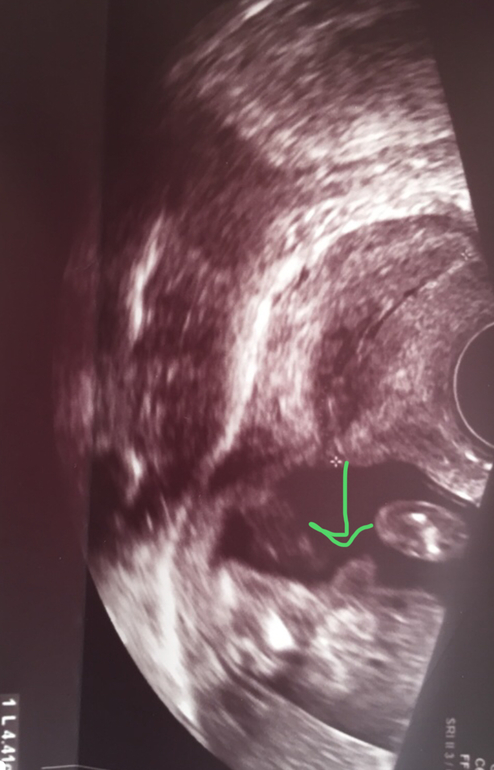

Но потом дома села снимки смотреть (ниже) и половой бугорок какой то слишком торчащим показался. Первое фото это снизу между ножек, сказали половые губки, а вот второе фото сбоку половой бугорок, он разве не мальчуковый? Срок 16.4

На таком сроке обычно хорошо уже видно пирожок или пушка) 😁Может быть не половой бугорок все же на фото?